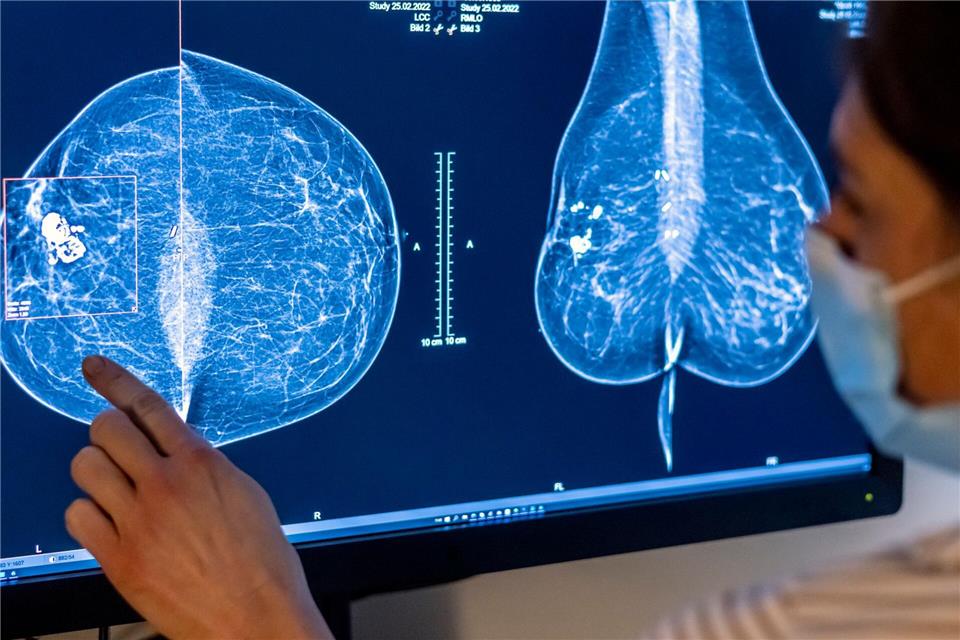

Insgesamt 914.050 Frauen im Alter von 50 bis 69 Jahren hatten im vergangenen Jahr einen Anspruch auf Früherkennungsuntersuchungen im Rahmen des Mammografie-Screenings.Hannibal Hanschke/dpa

In Hessen hat im vergangenen Jahr gut die Hälfte der im Rahmen des Mammografie-Screenings eingeladenen Frauen zwischen 50 und 69 Jahren an den Brustkrebs-Früherkennungsuntersuchungen teilgenommen. Das sagte Karin Bock, Programmverantwortliche Ärztinund Leiterin vom Referenzzentrum Mammographie SüdWest, der Deutschen Presse-Agentur. Als zentrale Einrichtung betreut das Zentrum das Programm in Hessen, Baden-Württemberg, Rheinland-Pfalz und dem Saarland.

Bock empfahl Frauen, den Untersuchungen in den zertifizierten Screening-Zentren auf jeden Fall den Vorzug zu geben. Es handele sich um ein qualitätsgesichertes, organisiertes und bundeseinheitliches System. Bei jeder Untersuchung schauten zwei besonders geschulte und qualifizierte Ärztinnen oder Ärzte auf die Bilder. Diese müssten als Vorgabe pro Jahr jeweils mindestens 5.000 solcher Bilder sichten und beurteilen. „Die Anforderungen sind so hoch, weil wir Frauen untersuchen, die zu diesem Zeitpunkt keine Krankheitssymptome haben.“

Auch das hessische Sozialministerium hebt die Bedeutung von Früherkennungsmaßnahmen bei Brustkrebs hervor. Werde die Erkrankung in einem frühen Stadium entdeckt, bestehe eine gute Chance auf einen günstigen Verlauf. Jährlich erhalten nach Angaben des Ministeriums rund 4.900 Frauen in Hessen die Diagnose Brustkrebs.